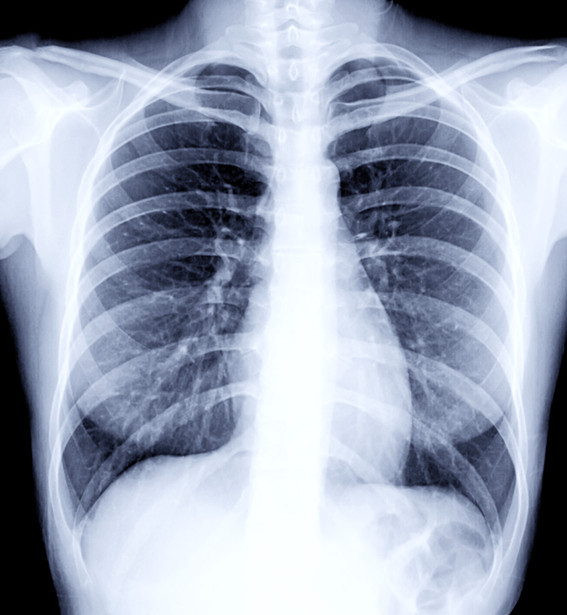

वैदेशिक रोजगारीको लागि अनिवार्य हुने स्वास्थ्य परीक्षणमा Chest X-ray गरिन्छ। यसमा फोक्सो (lungs) को अवस्था हेर्ने गरिन्छ।

छातीमा दाग भन्नाले प्रायः फोक्सोमा पुरानो रोग, संक्रमण वा चोटपटकपछि बाँकी रहेको ‘scar’ (घाउको निशान) लाई जनाउँछ। यो दाग प्रायः सामान्यतया मानिसलाई थाहा नहुने गरी हुन्छ र X-ray गर्दा मात्र देखिन्छ।

- रोग निको भए पनि X-ray मा सानो वा ठूलो दाग जीवनभर देखिन सक्छ।

“Chest X-ray मा देखिने दाग सधैं सक्रिय रोगको संकेत होइन। धेरै पटक रोग पुरानो भएर निको भइसकेपछि पनि दाग देखिन्छ। तर वैदेशिक रोजगारमा स्वास्थ्य परीक्षण गर्ने संस्थाहरू अत्यन्तै कडाइ गर्छन्। उनीहरूले रोग सक्रिय छैन भनेर बुझ्दा पनि स्वीकार नगर्ने अवस्था हुन्छ।”